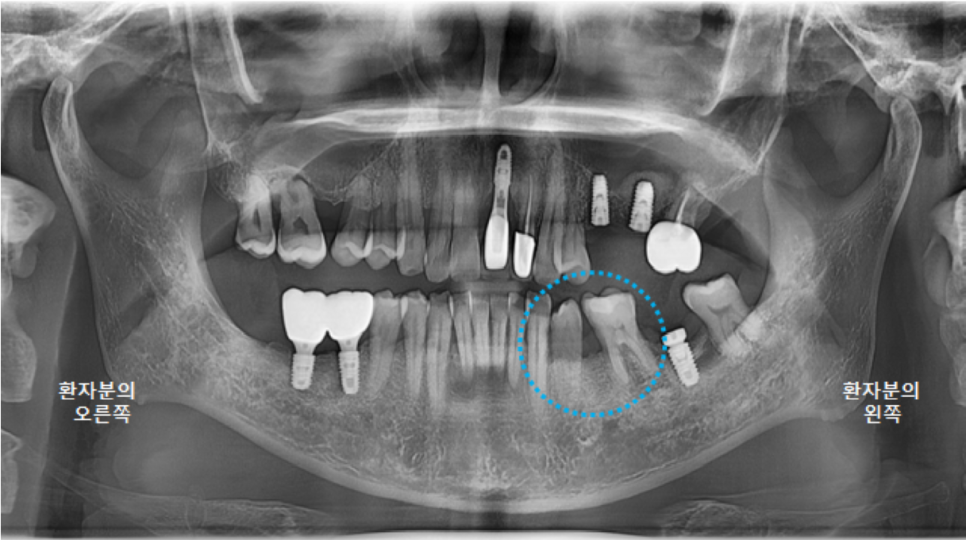

전체적인 구강 판단을 위해

파노라마 엑스레이 사진을 찍었습니다.

왼쪽 큰앞니도 빠져있지만,

오른쪽위 큰어금니, 오른쪽 아래 큰어금니도 발치된 상태였고,

왼쪽 위 브릿지 상태도 좋지는 않았습니다.

왼쪽 아래 큰어금니 하나는 뿌리만 남은 상태였어요.

그리고 다시 파노라마 엑스레이를 촬영했습니다.

최상의 컨디션은 아니지만,

어느정도 치유가 되었기에 3차원 CT 촬영 후, 왼쪽아래 큰어금니 임플란트 수술을 진행하도록 합니다.